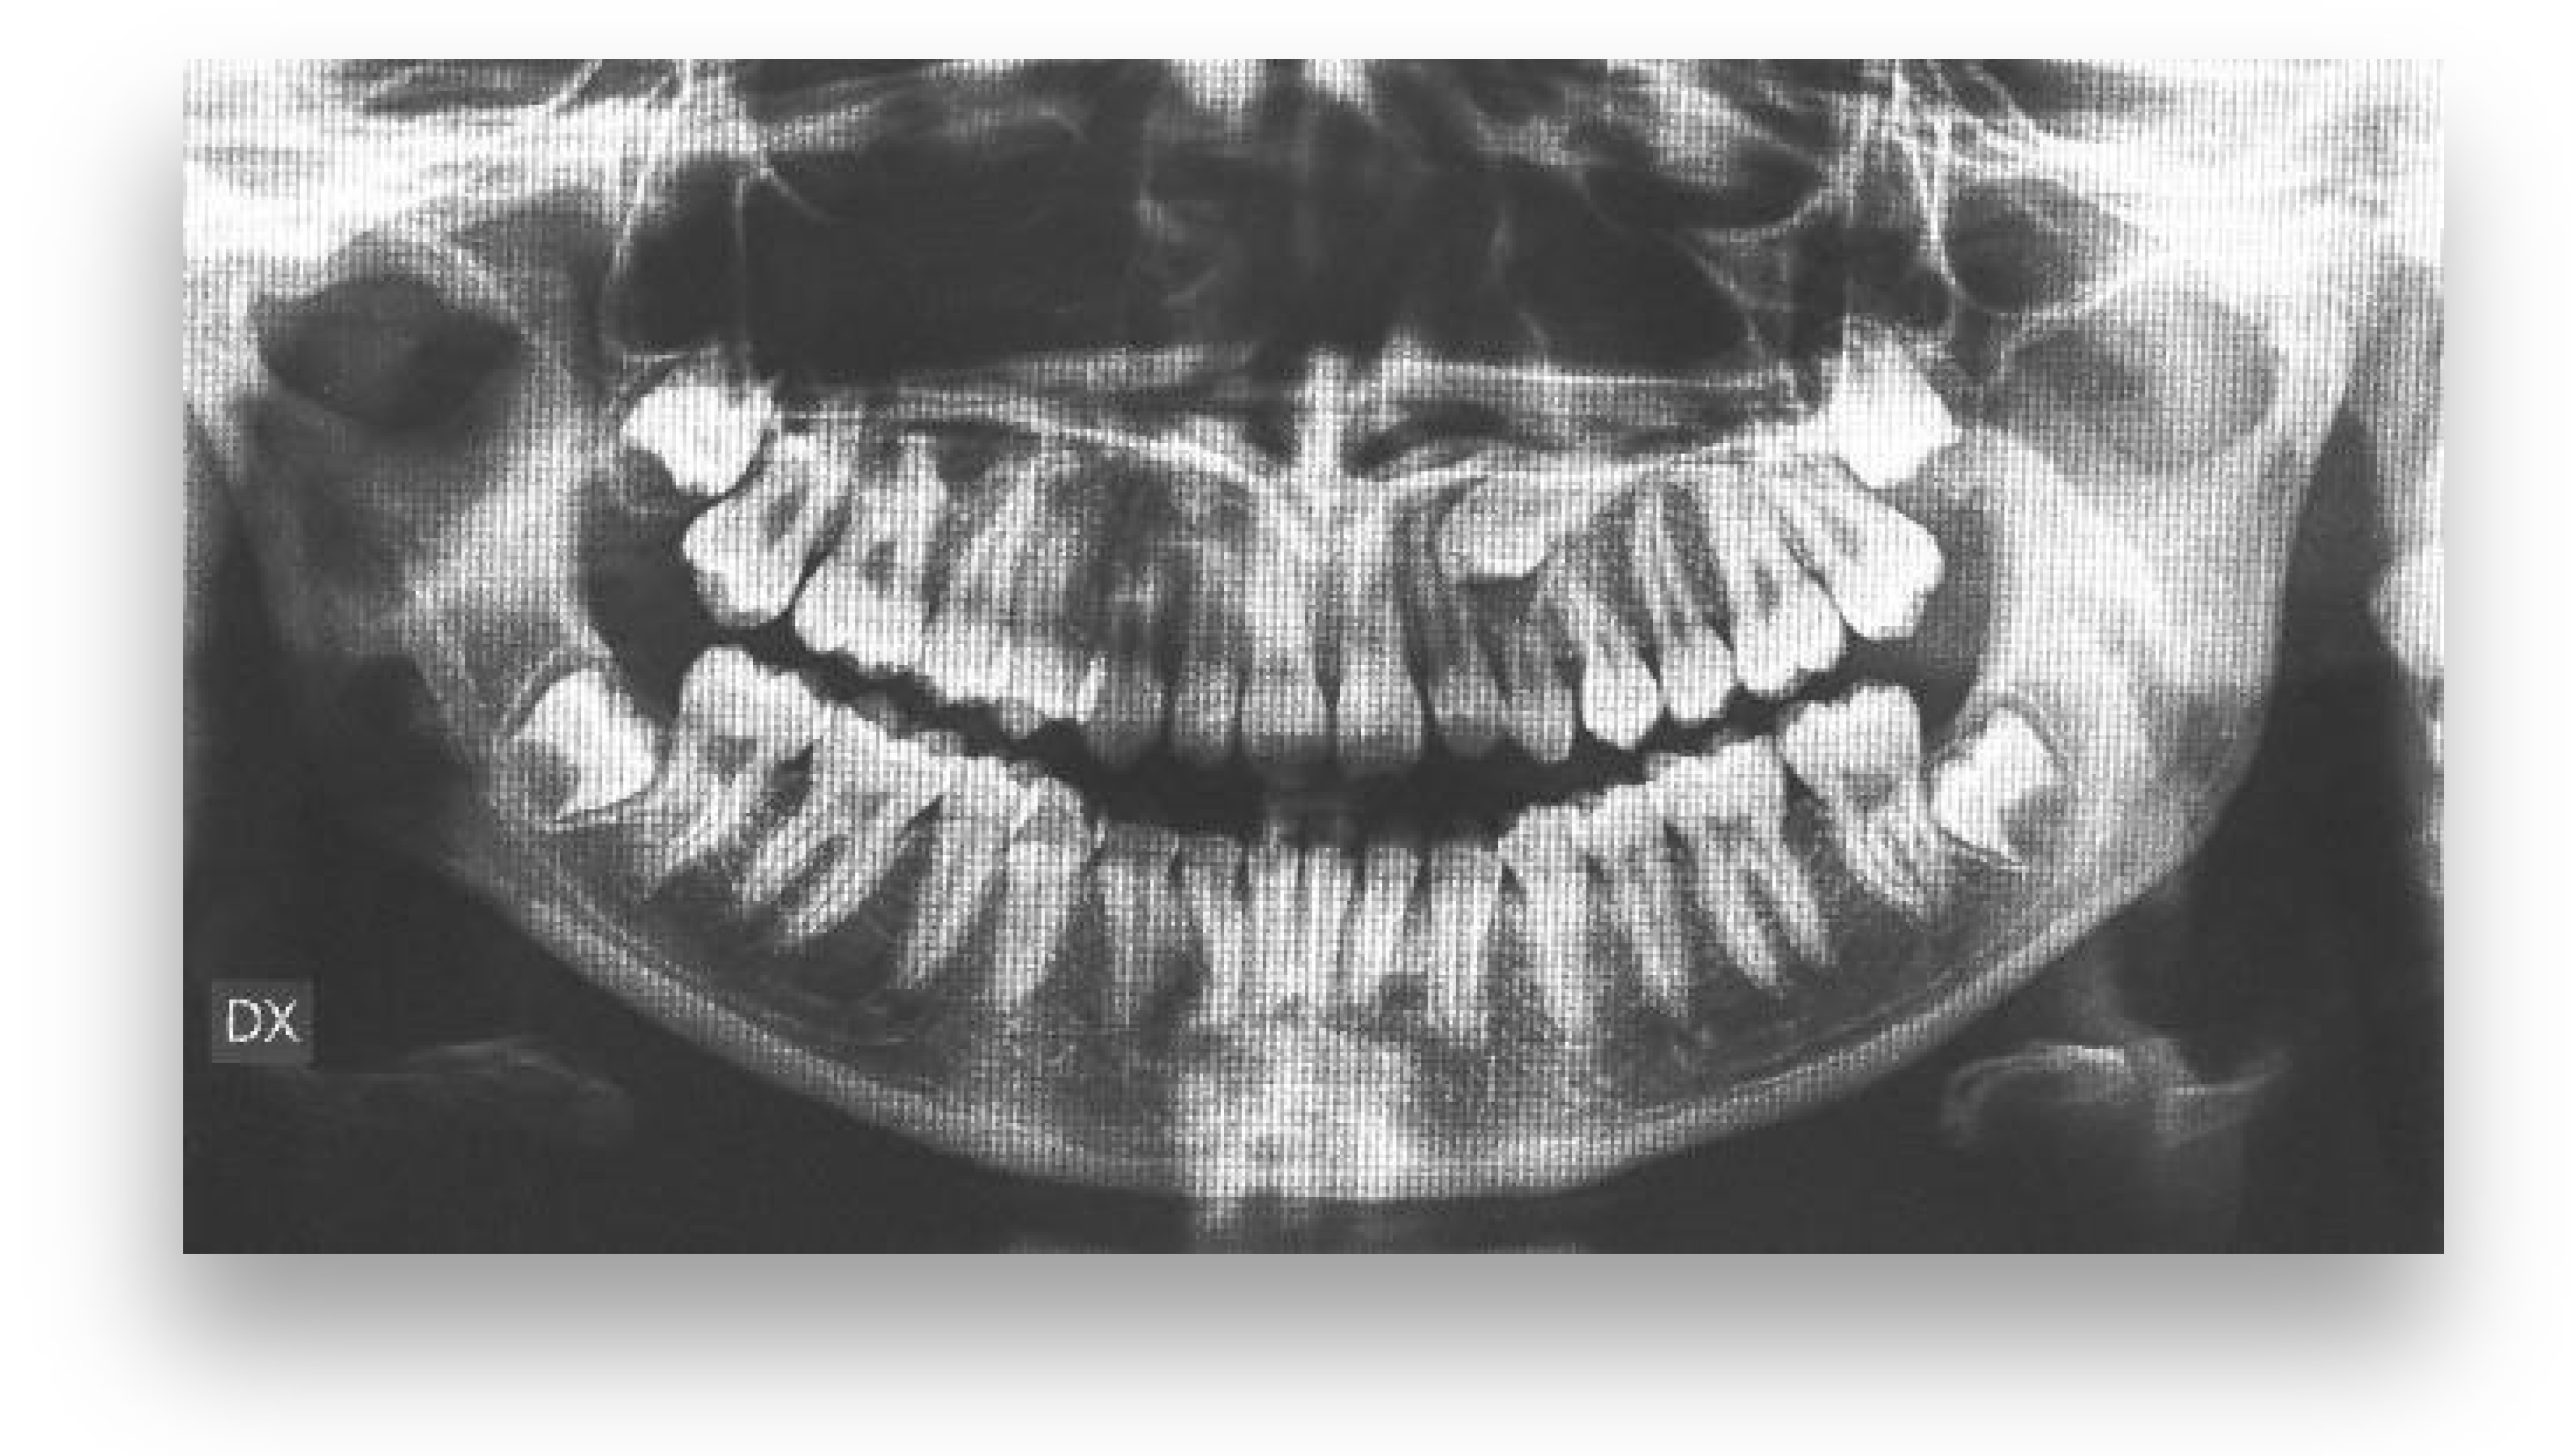

An 18-year-old female patient was referred, complaining of unpleasant smile. She presented good general health and no systemic or congenital diseases. From a frontal view, the patient presented a well-proportioned three-thirds of her face and no evidence of asymmetry. From the lateral view, the profile appeared convex with well-represented nasolabial angle, labiomental sulcus, and lip competence. Intraorally, the patient showed a Class II malocclusion with the molar Class I relationship, edge to edge canine relationship on both sides, increased overjet, overbite, and the retention of the 63. Panoramic, lateral headfilm, and dental cast records were taken (Figure 11).

An 18-year-old female with dentoskeletal Class II with impacted upper left canine before treatment.

The initial cephalometric analysis showed a skeletal Class I relationship (ANB, +2.6°) and mesodivergent pattern with the proclination of the upper (I/ANS-PNS 118.8°) and lower (i/GoGn:102.2°) incisors. All the radiographic findings, the age of the patient, the prolonged deciduous retention, and the risk of root resorption of the adjacent tooth, led clinicians to conclude that the permanent canine would not erupt properly without intervention (Table 2).

The position of the impacted canine showed an alpha angle of 58° and the Ericson and Kurol II sector classification. No clinical symptoms on articular examination were detected (Figure 12).

Pre-treatment panoramic X-ray with the evaluation of alpha angle and sector according to the Ericson and Kurol classification.